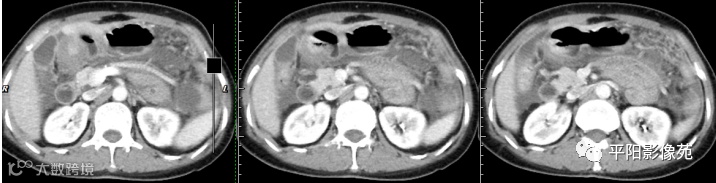

腹部增强 门脉期